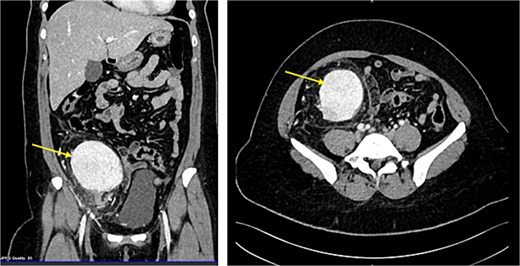

CT scan revealed evidence of large right iliac fossa soft tissue mass, measuring 8.5 × 8.2 × 8.4 cm, displacing the adjacent abdominal and pelvic organs with significant peri-lesional fat strandings. The mass shows homogenous hyper enhancement in post contrast with peripheral slight enhancing area [3.3 × 1.8 cm] with adjacent bowel loops tethering with peritoneal thickening. There were multiple adjacent para-aortic, right external iliac, and common iliac lymph nodes enlargement (Fig. 1). The mass vessels were arising from the right external iliac artery and vein (Fig. 2).

CT abdomen demonstrating the enlarged mass and its position by sagital and coronal sections (Arrow points at the mass).